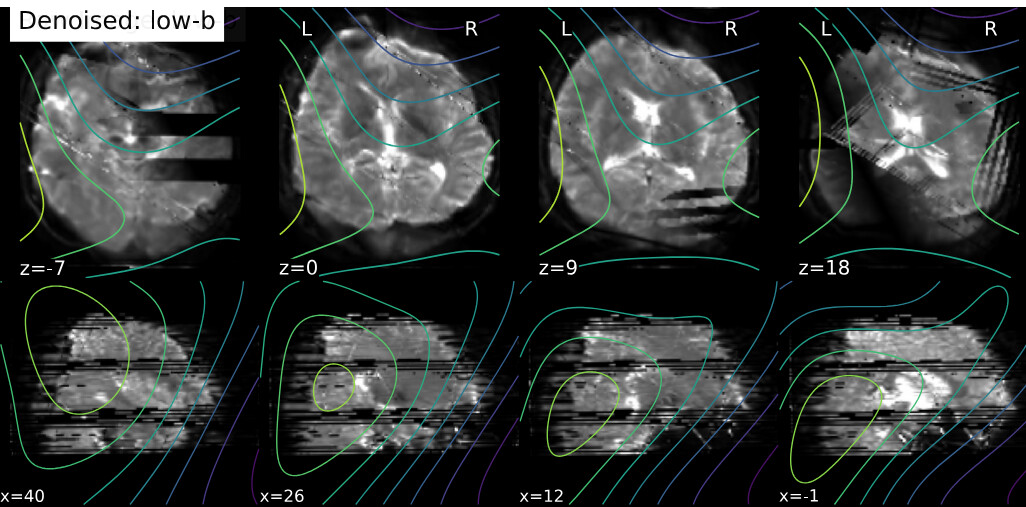

I’m using QSIprep 0.22.0 for preprocessing a dMRI dataset. For two subjects, the preprocessed data seem stripped -but not as the whole slices are missing- evident as early as in the denoising report:

If necessary, I have 75 slices with a multi-band factor of 3. I did some additional debugging by looking in the work directory, and I’m not sure whether this is important, but I noticed that dwi_preproc_wf/hmc_sdc_wf/extract_b0_series/eddy_corrected_LPS_b0_series_mean.nii.gz has cuts (see below), whereas it isn’t in other subjects.